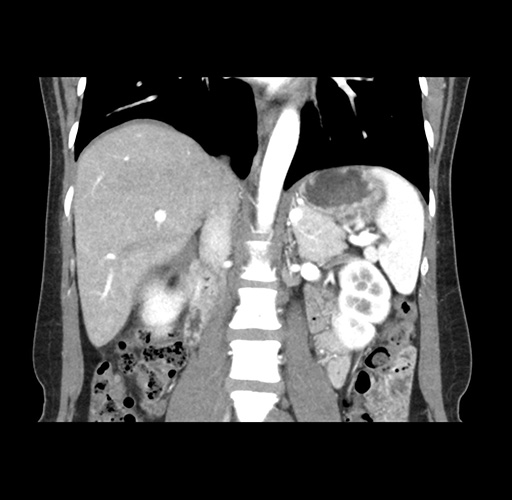

Imaging Analysis

Look through the patient's CT scan to identify any areas of concern for the necessary procedure.

Based on your CT findings, which issue(s) would give reason for "planned slowing down moment(s)" in this case?

Considering a standard left lateral sectionectomy procedure, what step(s) of the operation would you do differently in this case ?